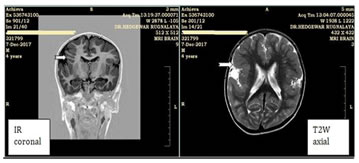

2

Image 2: A case of unilateral perisylvian syndrome.T1W inversion recovery coronal image showing polymicrogyria andT2W axial image shows broad right perisylvian cortex

in both patients. Loss of hippocampal architecture and hippocampal T2, FLAIR hyperintensity were present in both patients (100%). Persistent peritrigonalhyperintensities on T2W and FLAIR images were present in one patient and chronic ischemic foci in bilateral cerebellar, occipital parenchyma and periventricular white matter were present in one patient. Malformations of cortical development constituted 11 patients presenting with seizures. Out of them, Focal cortical dysplasia (FCD) was seenin8patients (72.7%). Corpuscallosaldysgenesis/agenesis(CCD/CCA), polymicrogyria and heterotopia constituted 3 patients (27.3%) each. Pachygyria and hemimegalencephaly (HMEG)constituted 2 patients (18.2%)while microcephaly constituted there mainder with1patient(9.1%). Five patients had multiple pathologies. One had unilateral perisylvian cortical dysplasia with polymicrogyria (Congenital unilateral perisylvian syndrome). One had Joubert syndrome, heterotopia and pachygyria. One patient had heterotopia, corpus callosum dysgenesis, focal corticaldysplasia and hypoxic is chemicencephalopathy. One patient had heterotopia, polymicrogyria, corpus callosum dysgenesis and hemimegalencephaly (HMEG). One patient had hemimegalencephaly (HMEG), agyria-pachygyria with polymicrogyria. Thus, Focal cortical dysplasia (FCD) was the most common pathology in patients with malformations of cortical development.